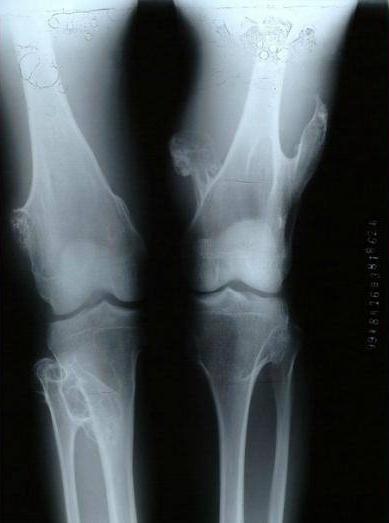

男性多发,肿瘤分布广泛且相对对称。在全身任何存在软骨的骨骼中几乎都有可能发生。由于肿瘤多发,所以很难依据外科手段全部切除。多表现为全身多发的骨性包块,常伴有骨骼短缩和畸形,如膝、踝、肘、腕关节的内外翻畸形。影像学上和单发的骨软骨瘤基本相同,只是肿瘤数量上的不同及存在骨骼畸形而已。